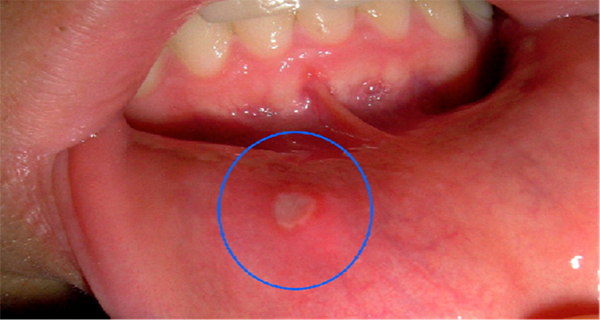

Emri mjekësor i ulcerave në gojë është “stomatit aftoz” që do të thotë “plagë e zjarrtë” dhe dalin rreth zgavrës së gojës. Këto ulcera janë të vogla, por shkaktojnë dhimbje të mëdha, madje shpeshherë pengojnë edhe gëlltitjen e ushqimit. Ulcerat janë infeksione virale që zgjasin disa ditë ose 1 javë, por ndonjëherë mund të zgjasin edhe më gjatë nëse nuk trajtohen.